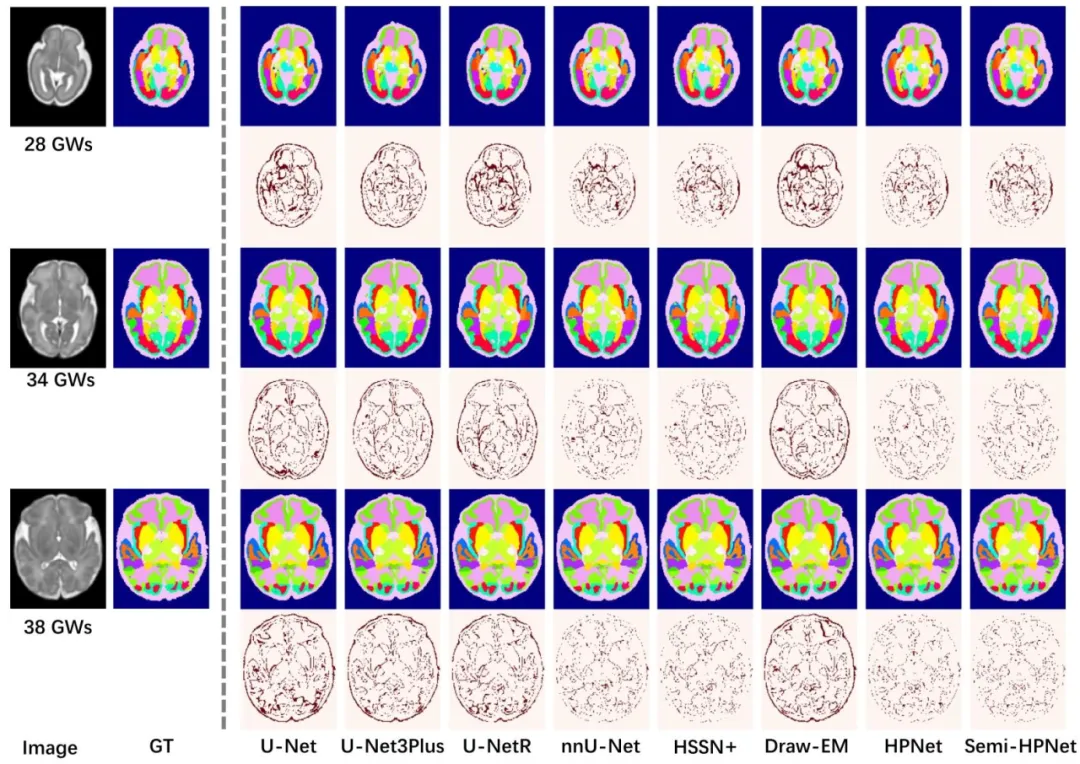

Fig. 6. Qualitative results of different methods on subjects at 28 GWs, 34 GWs, and 38 GWs. The even rows display difference maps

图6 不同方法在妊娠28周、34周和38周样本上的定性结果。偶数行展示差异图。